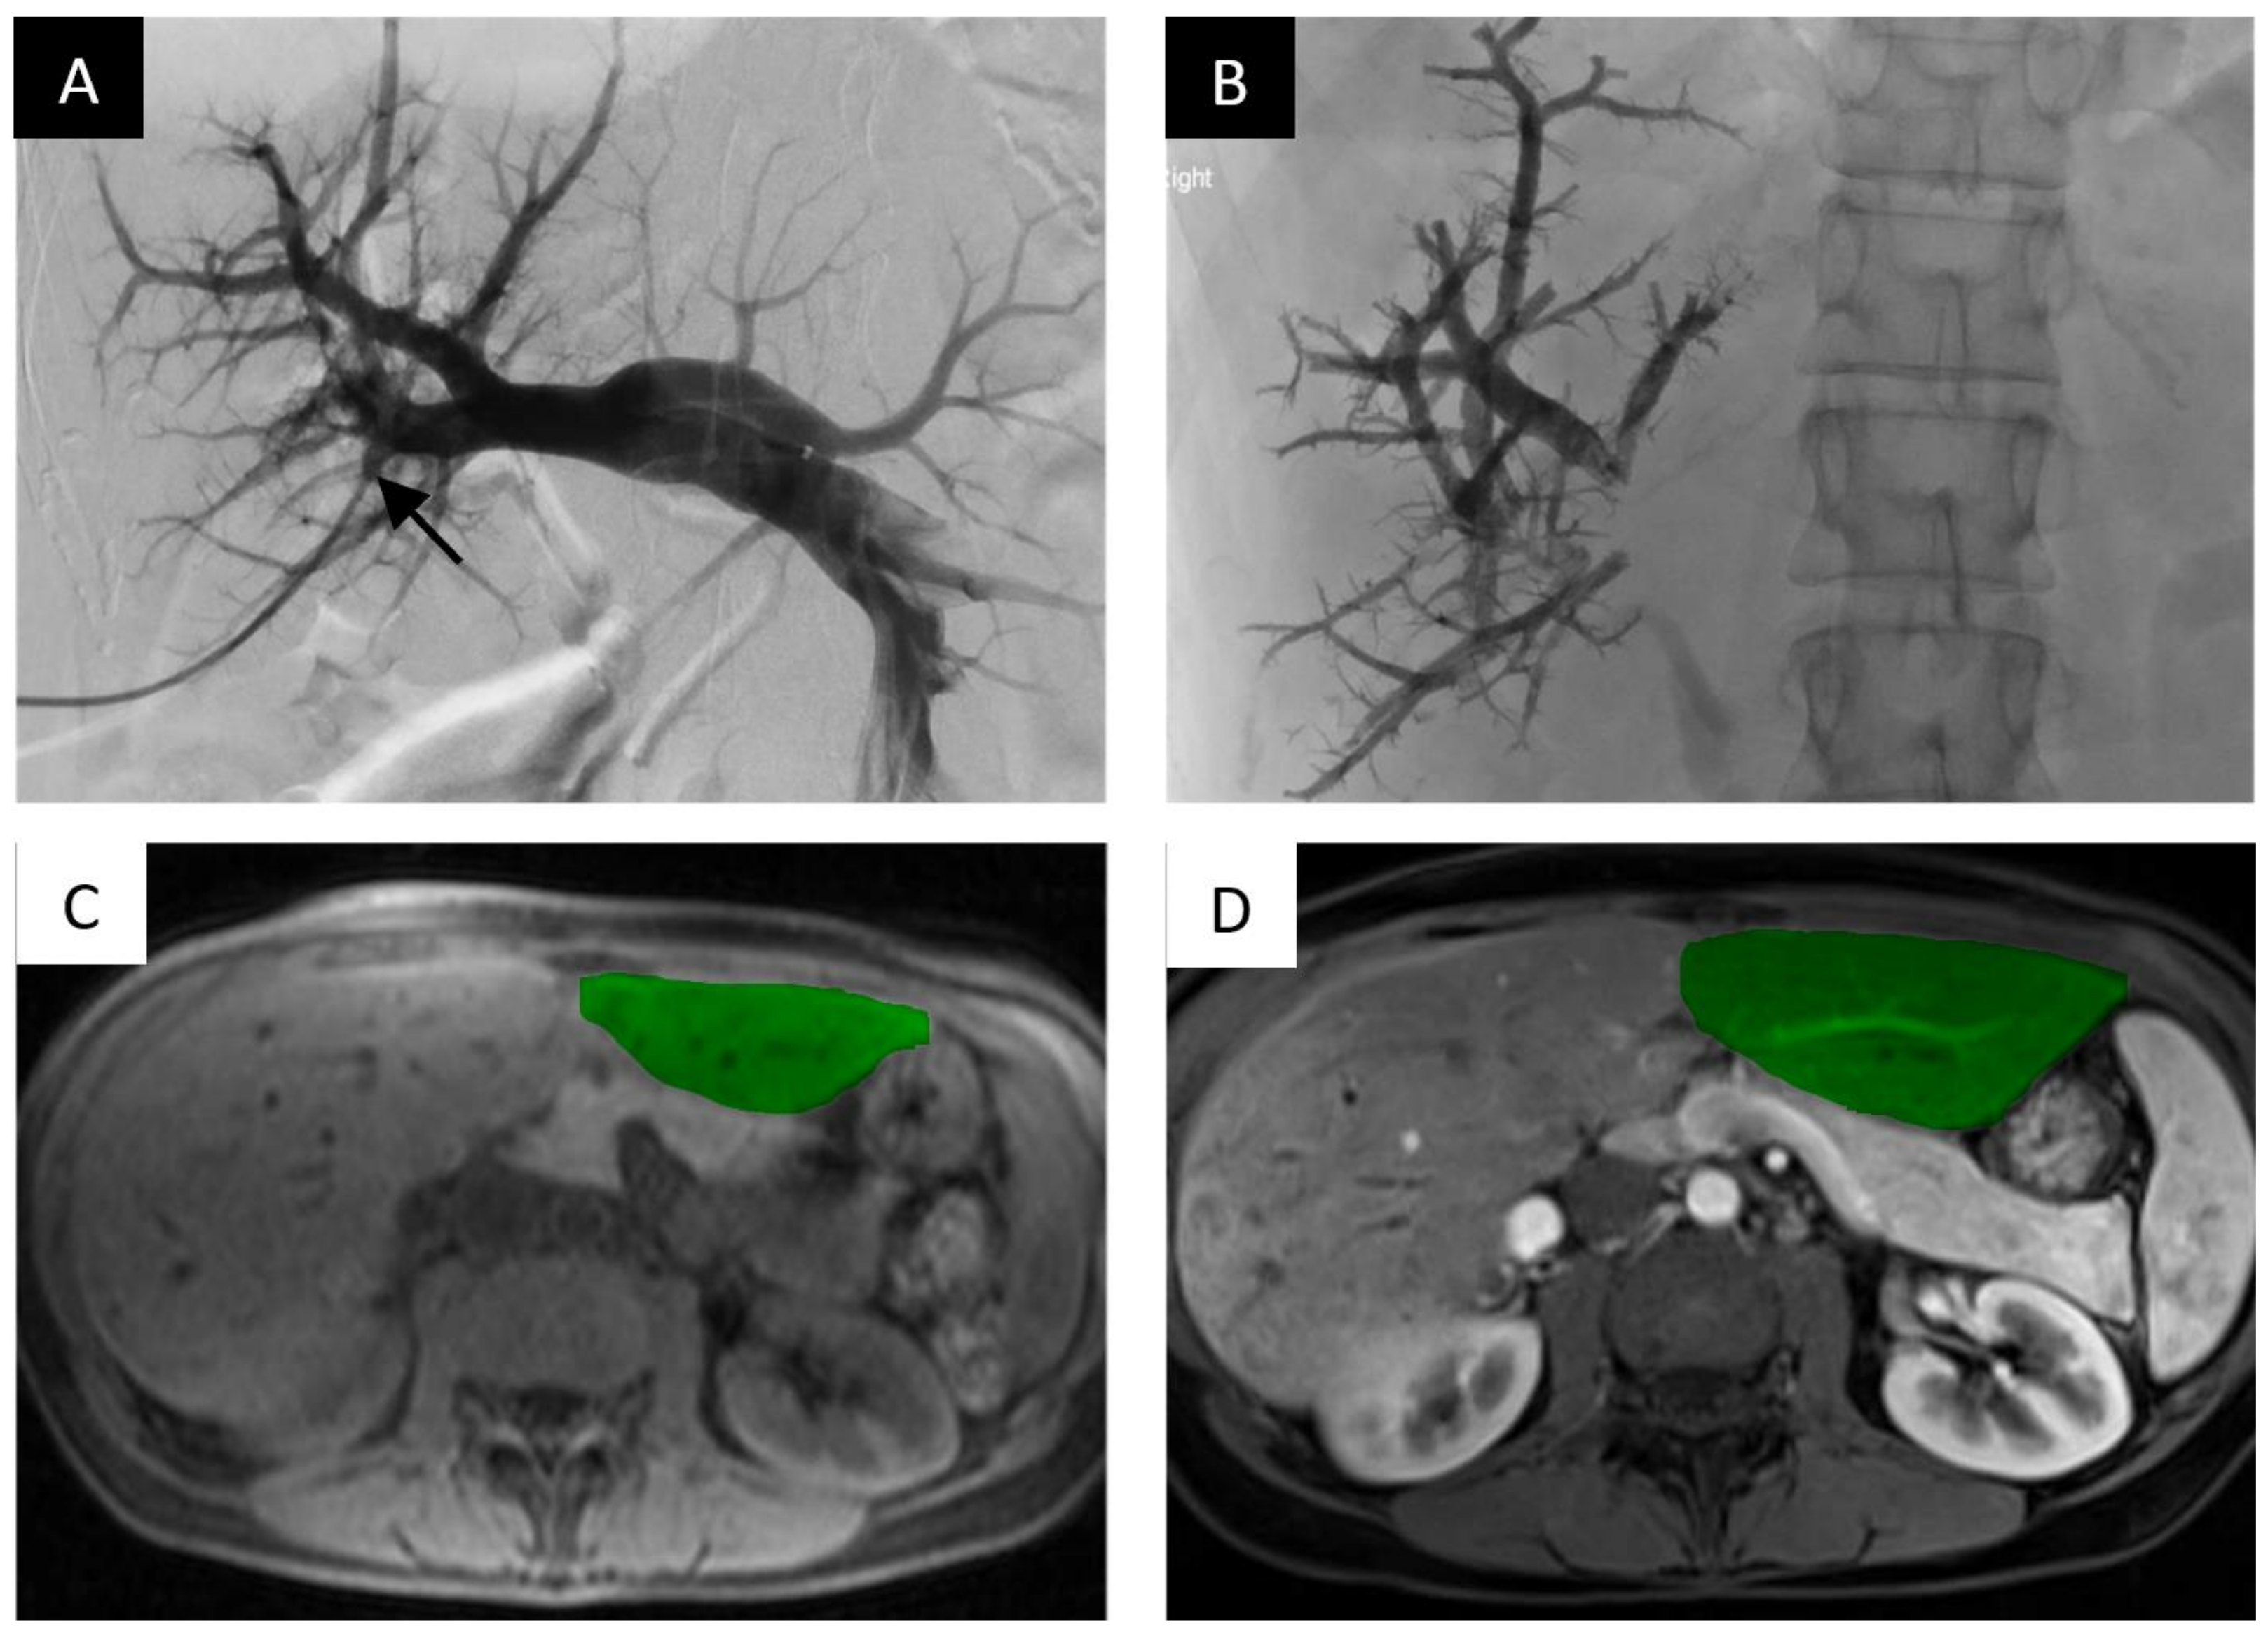

nBCA glue is a liquid embolic agent that has been shown to be effective for PVE and is commercially available in small aliquots (typically 1 mL vials). The embolic agent polymerizes when it comes into contact with an ionic agent and forms a permanent bond to adjacent structures. Typically, the agent is diluted with lipiodol which slows polymerization and allows the embolic agent to be radio-opaque on fluoroscopy (Figure 2).

Portal vein embolization of the right portal vein branch with nBCA glue and lipiodol demonstrates FLR hypertrophy. PVE of the right intrahepatic portal vein with nBCA glue with lipiodol. (A) Digital subtraction portography via side hole catheter in the main portal vein. Access gained into the portal system via anterior right portal vein branch (black arrow). (B) Final image, post-embolization of the right portal vein branches filled with radio-opaque nBCA glue. (C) Axial T1-weighted non-contrast magnetic resonance imaging (MRI) slice at the level of the hepatic parenchyma demonstrating the pre-embolized liver, with the non-hypertrophied left lobe highlighted. (D) Post-contrast axial T1 weighted MRI slice demonstrating noticeable hypertrophy of the left liver 45 days after embolization.

The ideal ratio of nBCA to lipiodol is not established but depends on how distal embolization needs to be achieved; ratios between 1:5 and 1:9 are used and administered in small 0.5 to 1.0 mL aliquots until stasis is achieved. When the portal embolization is complete, the punctured branch can be clotted off with either administration of additional nBCA and lipiodol or with manual compression while removing the access sheath. nBCA glue results in significant peripheral inflammation and produces effective portal occlusion.

Mukund et al. assessed PVE with nBCA glue and lipiodol in 28 patients [39]. The mean absolute FLR volume increased from 371 mL ± 87 to 567 mL ± 142, with a mean percentage increase of 52% ± 32 (p <0.0001). A total of 18 of the 28 patients (64.28%) underwent successful surgical resection 4–8 weeks post-PVE. Of the patients who underwent surgical resection, only one developed transient post-operative hepatic failure on post-operative day 5 but ultimately recovered on post-operative day 10.